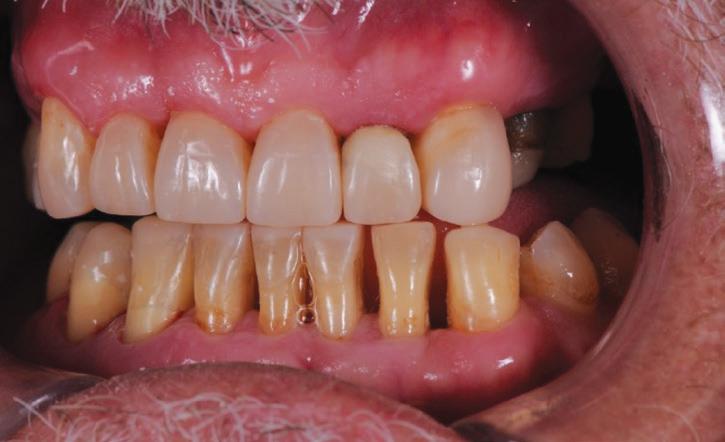

The first phase was to return the lost tooth structure, occlusion, vertical dimension and aesthetics with the composite buildups. Phase two was to remove the two premolars (#24 and #25) and allow soft tissue healing. Phase three was to place a dental implant in the site of the #25 and restore it with a 2-unit cantilever bridge.

In the present case, as all of the molars were missing and direct composites were to be used instead of crowns, the author proceeded by first restoring the maxillary anterior teeth. These anterior tooth forms were shaped according to aesthetically determined length and form, by free-hand bonding procedures. Once these teeth were restored, it was possible to then determine the appropriate length and form of the lower incisor teeth, to support the new vertical dimension. Finally, with all of the anterior teeth restored, the remaining premolar teeth were then restored to create stable occlusal contacts, at this new vertical dimension. The final phase of treatment would then be to surgically remove the infected upper left premolars and place the implant and cantilever bridge.

Importantly, the stability of the occlusion was re-established with creation of occlusal contacts on each tooth, and the re-introduction of canine and incisal guidance, to control lateral and protrusive forces (Figs. 20, 21, 22, 23).